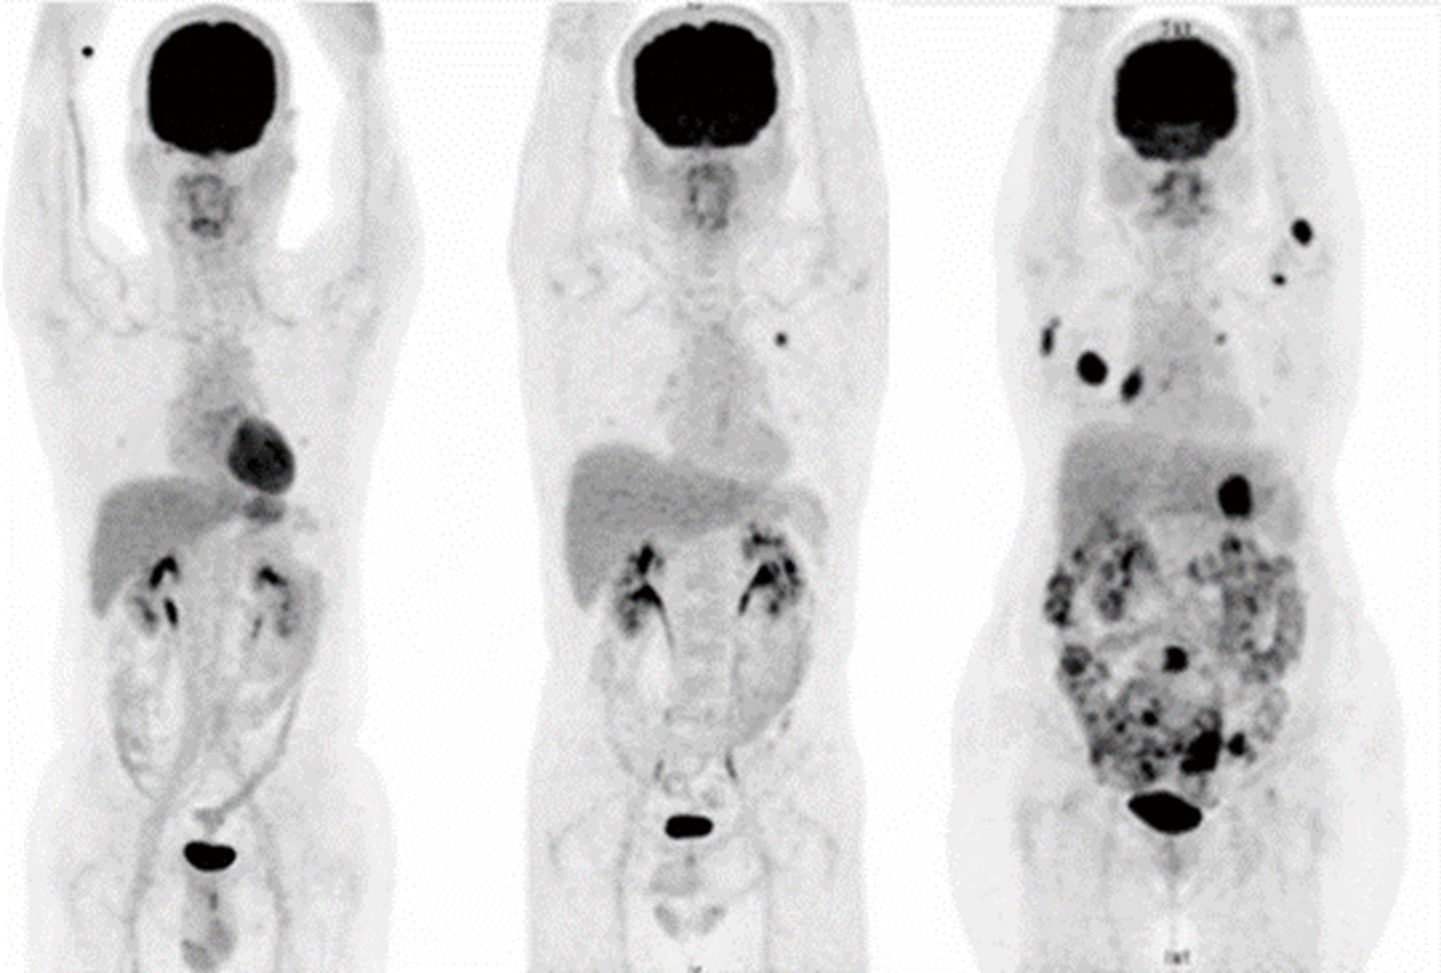

正子斷層造影應用於癌症、心血管及神經系統疾病等領域,搭配氟-18標記的葡萄糖 (F-18 FDG)可進行早期癌症及遠端轉移性病灶偵測,相比於傳統影像診斷率更高。目前健保給付項目包含淋巴癌、頭頸癌、甲狀腺癌、乳癌、肺癌、食道癌、大腸直腸癌、黑色素癌、子宮頸癌。除了傳統的氟化葡萄糖正子斷層造影外,近年也發展出各式正子藥物,應用於攝護腺癌及神經內分泌腫瘤的診斷治療(Theranostic),以及神經退化性疾病之診斷。